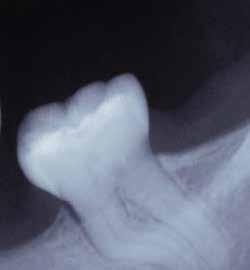

Egy 38 éves nőbeteg a korábban kezelt jobb felső második kisőrlőfogából (1.5) kiinduló mérsékelt fájdalom miatt jelentkezett rendelésünkön. A kórtörténetében jelen panasza szempontjából releváns információ nem szerepelt. A beteg a klinikai vizsgálat során vertikális kopogtatásra enyhe érzékenységet jelzett. A kérdéses fog körül mérhető szondázási mélység és a fogmobilitás fiziológiás volt. Periapicalis röntgenfelvételen egy, a fog gyökércsúcsán túl presszálódott betört gyökérkezelő műszerből származó eszközfragmentumot láttunk (2. a. ábra). A preoperatív CBCT-felvétel a buccalis csontlemez épségét igazolta (2. b-c. ábra). A fog revíziója öt hónappal korábban történt. A már előzőleg gyökérkezelt, gyökértömött, majd revideált 1.5-ös fog esetében a diagnózisunk periodontitis periapicalis symptomatica volt. A periapikális elváltozás kezelése érdekében navigált endodonciai mikrosebészeti beavatkozást végeztünk.

a-m. ábrák: Preoperatív röntgenfelvétel (a) és preoperatív CBCT-felvétel a jobb felső 5-ös (1.5) fogról, sagittalis (b) és axialis (c) nézetek. Az intraorális szkennelés során kapott STL-fájl (d). A 1.5-ös fog navigált endodonciai mikrosebészeti beavatkozásához tervezett sablon (e). A 1.5-ös fog navigált endodonciai mikrosebészeti beavatkozásához nyomtatott sablon (f). Teljes vastagságú mucoperiostealis lebenyt emeltünk (g). A sablont a helyére illesztettük, és a csontablak határait jelöltük (h). A fog gyökerén kívül eső, betört eszköz a 1.5-ös fog periapicalis régiójában (i). Az eltávolított betört eszköz (j). A rezekció, retrográd preparáció és a TotalFill BC RRM Fast Set Putty anyaggal elkészített retrográd gyökértömés utáni röntgenfelvétel (k). A lebenyt varratokkal rögzítettük (l). A kétéves kontroll során készített röntgenfelvétel (m).

gítségével tovább módosítottuk. Az így kapott sebészi sablon egyértelműen meghatározta a periapikális terület eléréséhez szükséges csontablak határait (2. e-f. ábra) Helyi érzéstelenítést követően teljes vastagságú mucoperiostealis lebenyt képeztünk, majd a buccalis csont feltárását követően (2. g. ábra) a sablon segítségével bejelöltük a preparálandó csontablak határait (2. h. ábra). A csontablak kialakítása során Piezotome CUBE LED kézi-darabot alkalmaztunk, majd a leemelését követően a betört eszközt megkerestük (2. i. ábra) és eltávolítottuk (2. j. ábra). A rezekciót ultrahangos megmunkáló fejekkel (ACTEON) végeztük, majd retrográd preparáció következett.

A retrográd gyökértömés elkészítése során TotalFill BC RRM Fast Set Putty-t (FKG) használtunk (2. k. ábra). A lebeny széleit 5/0-s Prolene varratokkal egyesítettük (2. l. ábra). A varratok a műtétet követően 72 órával kerültek eltávolításra. A beteg két évvel később kontrollröntgen készítése céljából érkezett rendelőnkbe. A vizsgálat során a fog tünetmentesnek és funkcióképesnek bizonyult (2. m. ábra).